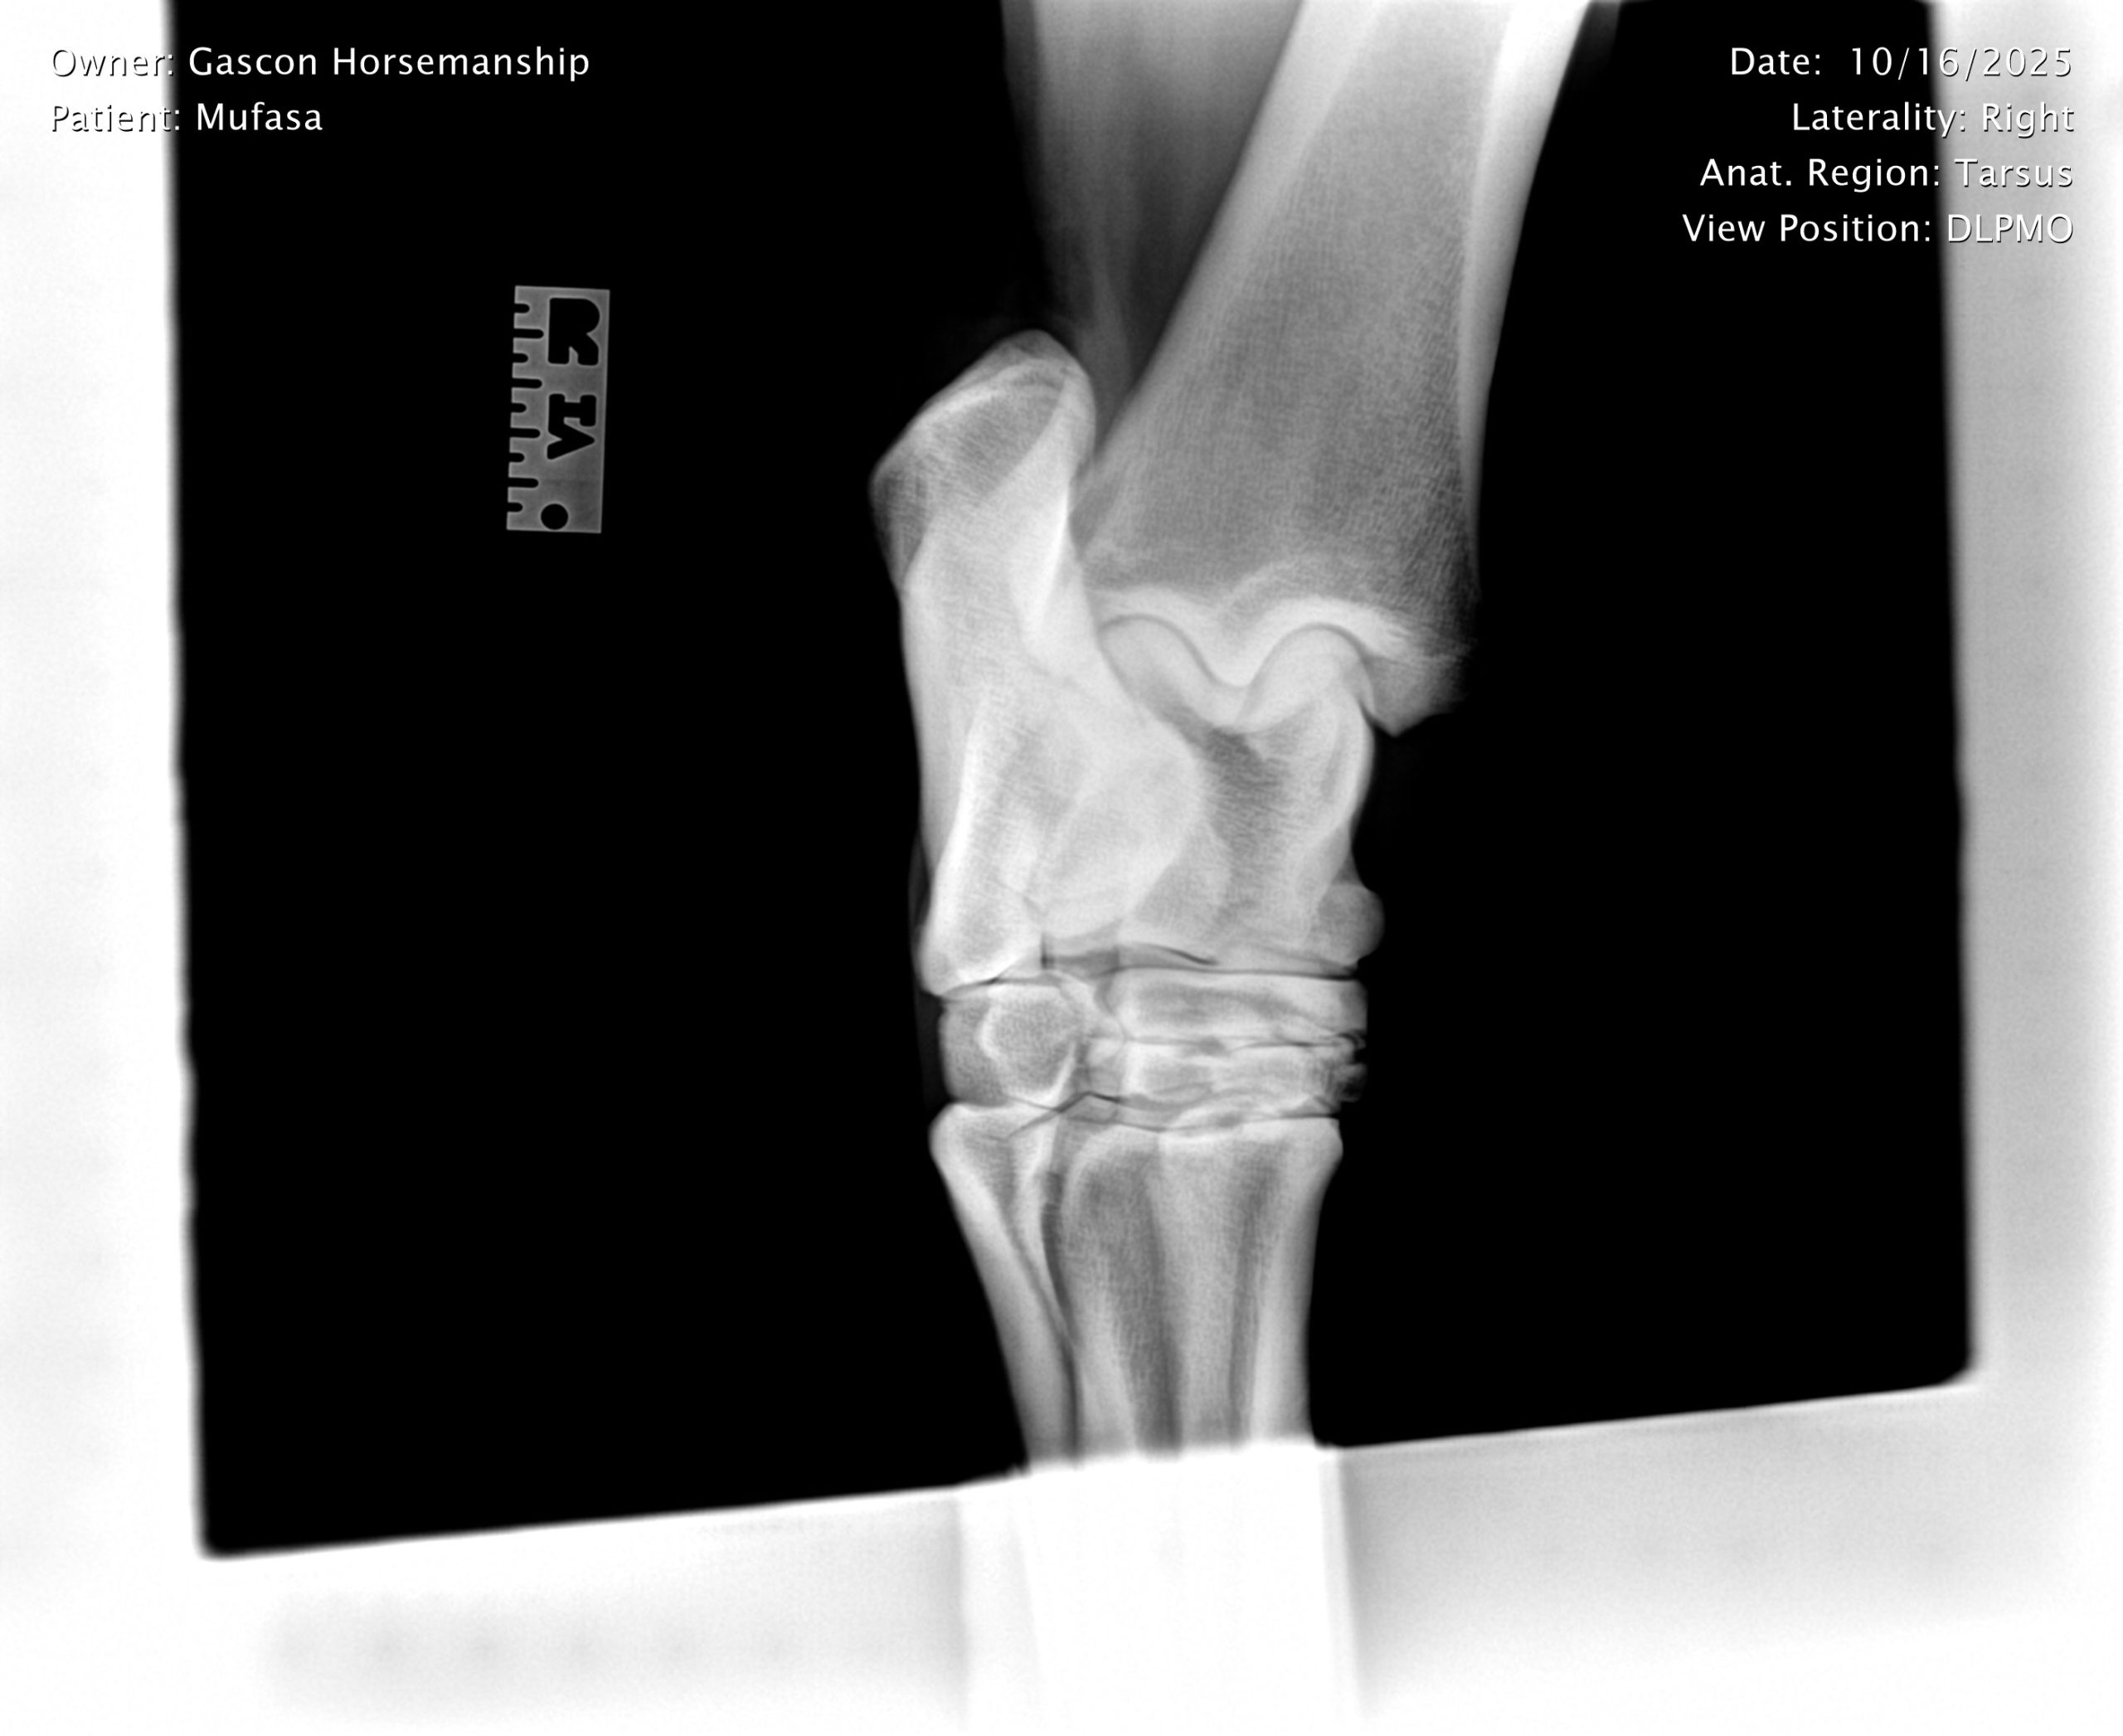

He already has a full pre-purchase exam on file, complete with 25 X-rays included in his album.